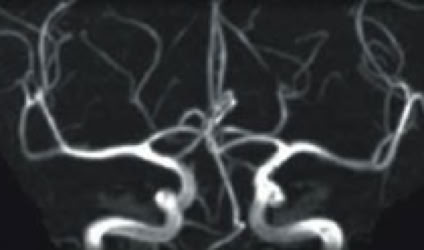

脳MRA

MRIは磁石を使った断層撮影です.磁場に身体が入ると,体内の水などを構成している水素原子核が磁気に共鳴して電波を発生します.それを受信し画像を作成します.CTとの大きな違いは ”放射線” を使用しないことです.また,造影剤を使わずに血管を描出することもできます.

頭痛・めまい・腰痛や肩こり・手足のしびれの原因検査,顔面や頭部の外傷,脳疾患後の管理や,クモ膜下出血の原因となる脳動脈瘤(脳の動脈にできるコブ)や,初期の脳梗塞の発見など,また,生活習慣病の方の病気の早期発見や予防にも効果的な検査です。